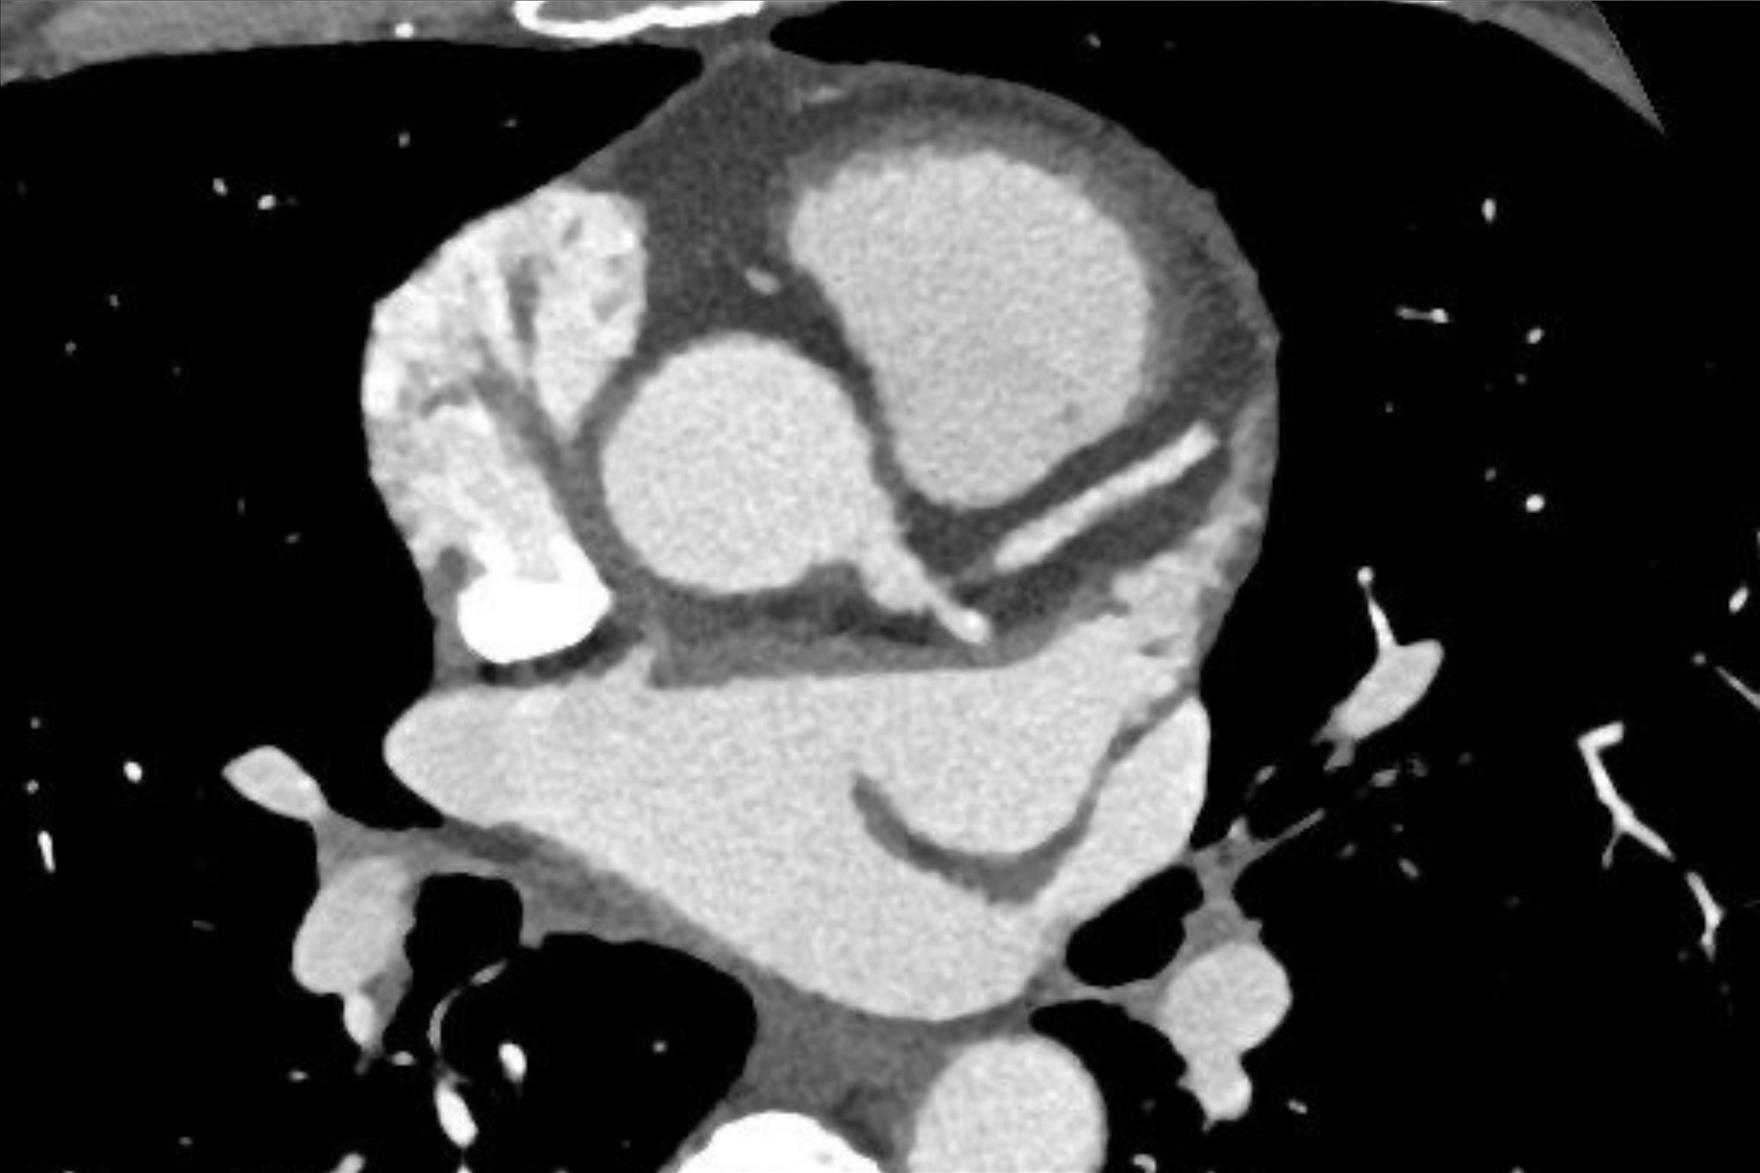

PAÜ Hastaneleri Radyoloji Anabilim Dalı Öğretim Üyesi Doç. Dr. Vefa Çakmak yaptığı açıklama da şunları söyledi: “Pandemi döneminde hayatımıza daha sık giren bilgisayarlı tomografi (BT), günümüzde tanı ve tedavi süreçlerinde hayati önem taşıyan bir görüntüleme yöntemi olarak kullanılmaya devam ediyor. Radyasyon içeren bu teknoloji, pek çok organın ayrıntılı şekilde incelenmesini sağlarken, acil durumlarda hızlı teşhis imkânı sunarak hayat kurtarıcı bir rol üstleniyor. Özellikle kanserin tanı ve takibinde, trafik kazaları, beyin kanamaları, kırıklar ve büyük cerrahiler öncesinde önemli bir yer tutuyor. BT ile kalbi besleyen damarların detaylı şekilde görüntülenmesi mümkün hale geliyor. Halk arasında ‘sanal anjiyo’ olarak bilinen bu yöntemle, kalpte işlem gerektiren damar tıkanıklıkları erkenden saptanabiliyor. Böylece hastalar, gereksiz klasik anjiyo işlemlerinden korunuyor. Aynı anda kalp duvarları, kalp içindeki pıhtı ya da tümör gibi oluşumlar ve ritim bozukluğuna neden olabilecek yapılar da değerlendirilebiliyor. Ayrıca, bu çekimler sırasında düşük dozla akciğer görüntülemesi de yapılarak yapısal akciğer hastalıkları, akciğer kanserleri ve göğüs kafesiyle ilgili kemik problemleri de tespit edilebiliyor. Çekim öncesinde hastanın böbrek fonksiyonlarını korumak amacıyla kreatin ve GFR gibi kan testleri yapılıyor. Hastanın mevcut hastalık öyküsü ve ilaç alerjileri sorgulanıyor. Kaliteli bir görüntü elde edebilmek için kalp atım hızının dakikada 70 civarına düşürülmesi gerekebiliyor; bu durumda nabız düzenleyici ilaçlar kullanılabiliyor. İşlem sırasında hasta monitörize ediliyor, göğüs bölgesindeki metal eşyalar çıkarılıyor ve yaklaşık 10–15 saniyelik nefes tutması isteniyor. Kardiyak BT çekimi 4–10 saniye sürüyor ve görüntülerin değerlendirilip raporlanması genellikle aynı gün içinde tamamlanıyor.”